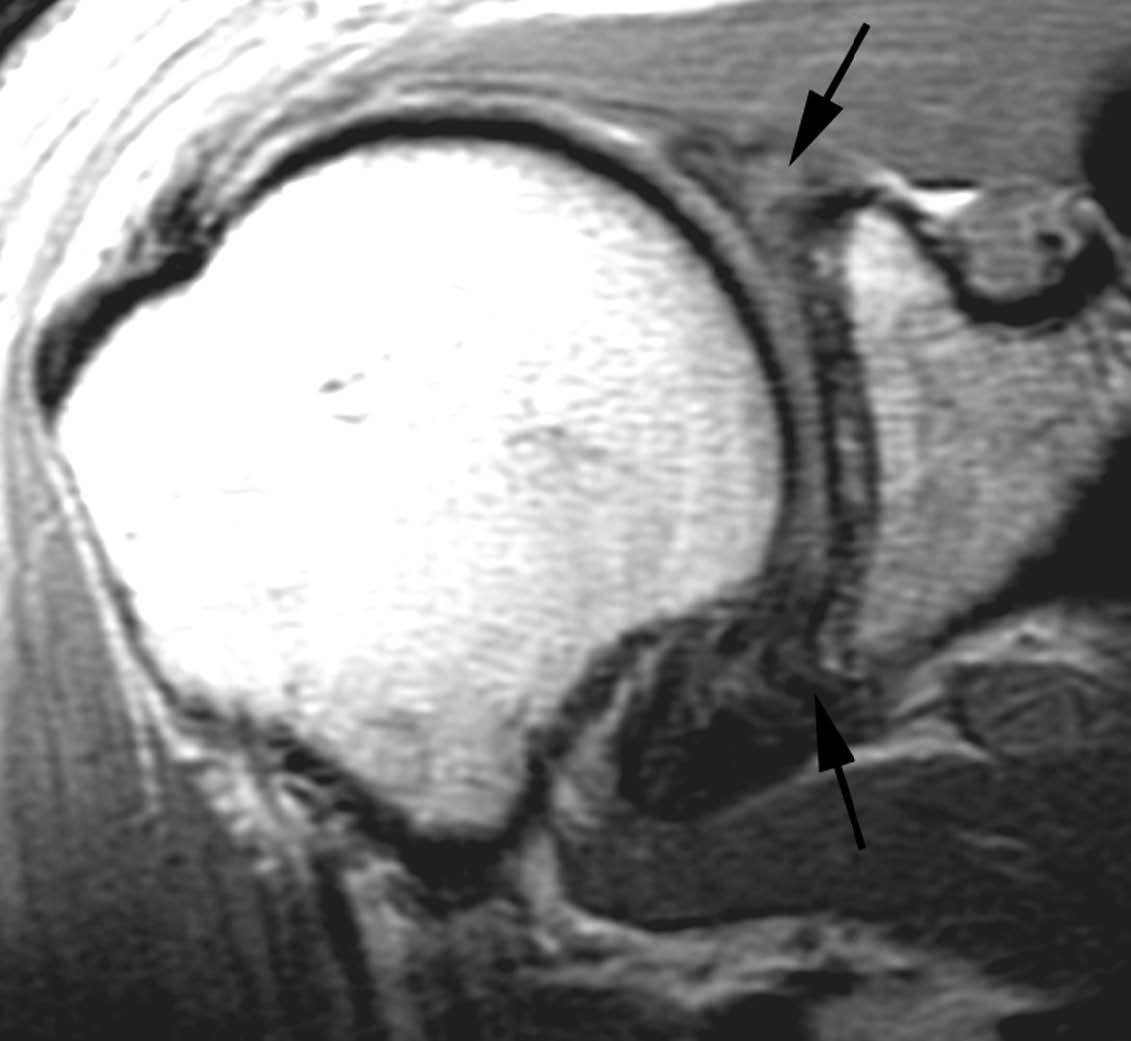

POLPSA (posterior labral periosteal sleeve avulsion)

Esta lesión se asemeja a la ALPSA, pero ocurre en el borde glenoideo posterior. El LG se halla desplazado hacia dentro y por detrás del borde glenoideo posterior. El mecanismo de producción del POLPSA es una dislocación posterior, y por tanto se puede encontrar también un Hill Sachs invertido19 (fig. 14).

. Artrorresonancia axial T1 con supresión grasa donde se observa una rotura del labio glenoideo posterior con desplazamiento posteromedial (flecha). Nótese la situación del labio glenoideo en comparación con una rotura sencilla, no desplazada, que se observa en la figura 13. Obsérvese la presencia de una lesión de Hill-Sachs invertida (cabezas de flecha), en relación con una dislocación posterior con reducción.Lesión de Bennett